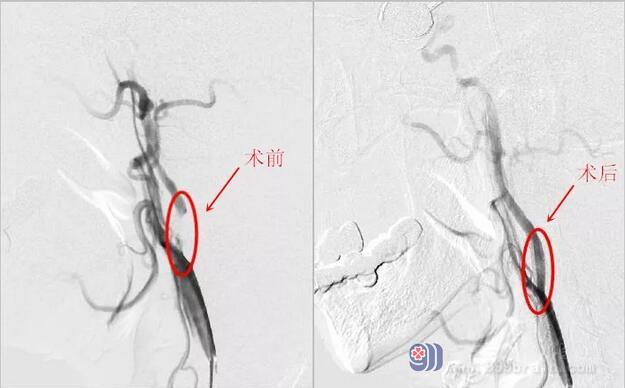

经过一番紧张有序的手术治疗,最后成功实现对颈内动脉狭窄处的扩张。通过对比术前、术后的造影影像,可以见到狭窄处得到明显改善,而且MR灌注成像也证实了颅脑已经恢复供血灌注,这对改善钟叔的预后起了重要作用。

术前术后DSA影像